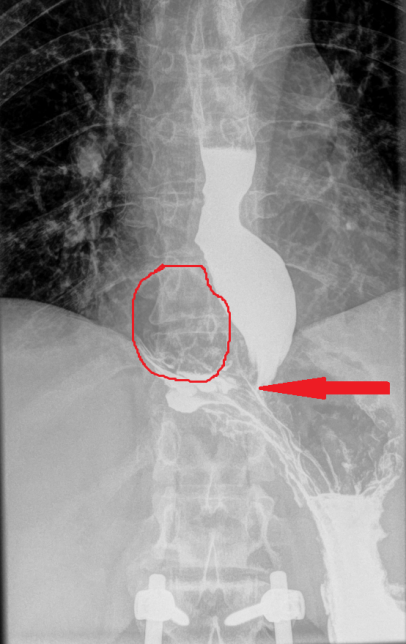

Abdominal CT scan. Red outline – Inflammatory fibroid polyp of the duodenum (Courtesy Dr. V. Penopoulos)